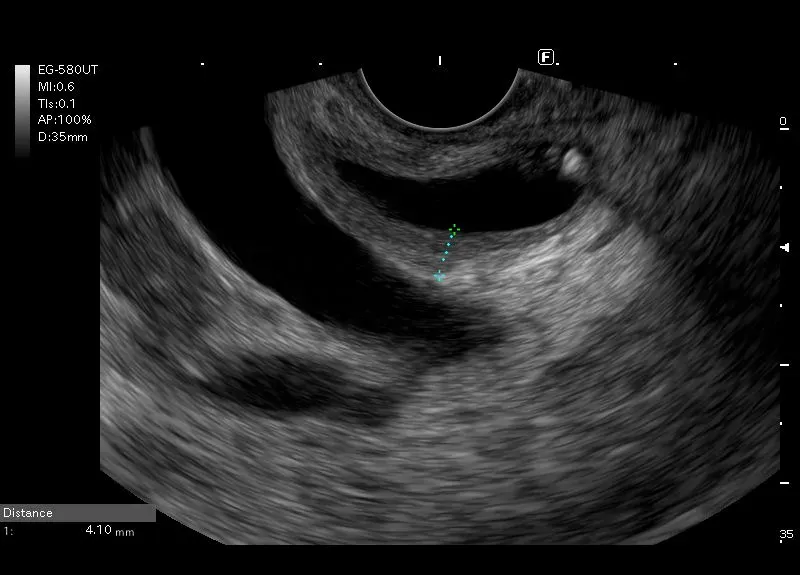

Przewód  żółciowy wspólny z pogrubiałą ścianą i widocznymi w świetle drobnymi, owalnymi i linijnymi  hyperechogenicznymi  odbiciami z niewielkim” brudnym” cieniem - obraz aerocholii powstałej po instrumentacji dróg żółciowych